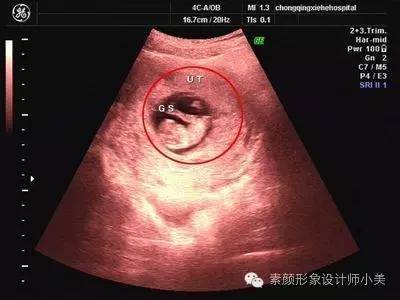

8周胎儿发育

第8周的胚胎大约有16毫米长,看上去挺像颗葡萄的。这时胚胎像跳动的豆子一样开始有运动。因为骨髓还没有成形,现在由肝脏来生产大量的红细胞,直到骨髓成形后去接管肝脏的作用。虽然身体很小但是心脏和大脑已发育得非常复杂了,胚胎的器官已经开始有明显的特征,各个不同的器官开始忙碌地发育,手指和脚趾间看上去有少量的蹼状物。牙和腭也开始发育,耳朵也在继续发育,胎儿的皮肤犹如纸一样地薄,可以清晰的看到血管。虽然在子宫里面你觉得还是处于无声无息的状态,其实胎儿现在已经会在里面做一些踢腿、伸腿、抬手、移动双臂的小动作了。

第一次产检:

一般在孕期第8周-12周时要进行第一次正式产检,此时医院会给每位孕妇建立一个档案,记录你整个孕期每次身体检查情况。所以第一次产检也俗称为“建档”。第一次产检的项目通常包括问诊,测量体重和血压,听胎心,验尿,验血,检查子宫大小等。会因各医院安排的不同和孕妇的具体情况而在某些项目上大同小异。